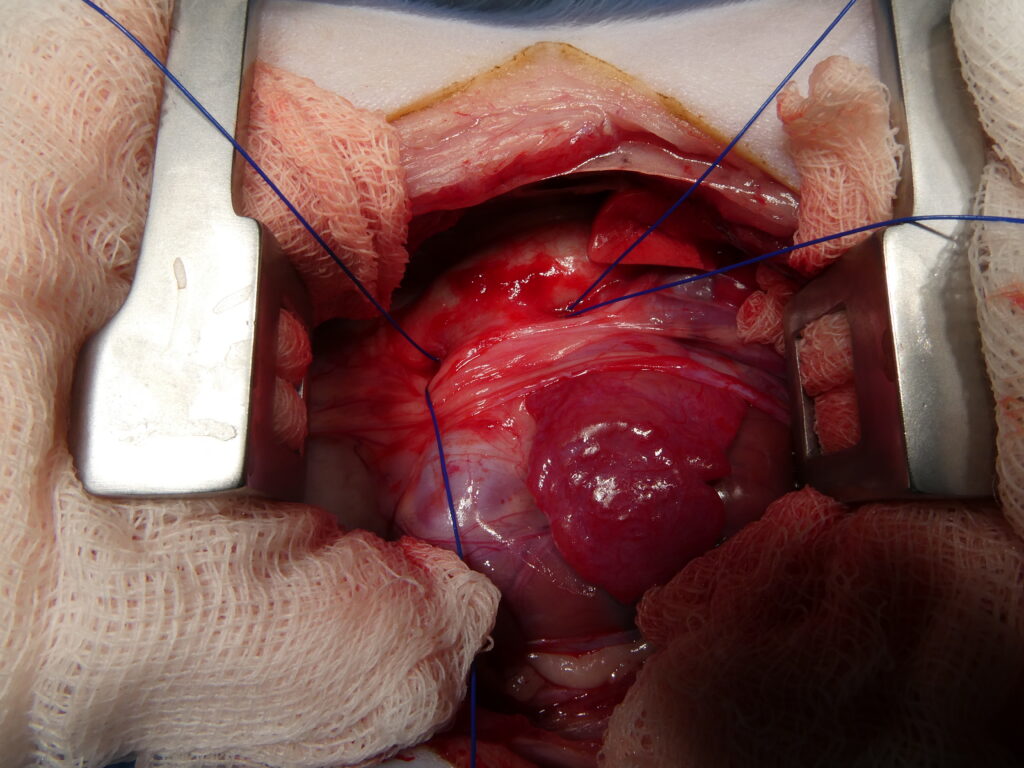

Traitement chirurgical de l’abcès par thoracotomie et épiplooplastie.

En haut à gauche, ouverture de l’abcès pulmonaire par thoracotomie intercostale en région caudale, avec ponction et aspiration initiale du contenu purulent, dans un contexte de dyspnée sévère liée à l’occupation d’environ la moitié de l’hémithorax gauche.

En haut au centre, aspect de la cavité de l’abcès après évacuation complète et nettoyage, mettant en évidence un espace résiduel important nécessitant un drainage durable.

En haut à droite, réalisation d’une laparotomie abdominale afin de prélever un segment d’épiploon destiné à être utilisé comme drain biologique.

En bas à gauche, tunnelisation sous-cutanée de l’épiploon entre la cavité abdominale et la cavité thoracique, permettant son transfert sans tension vers le site pulmonaire.

En bas au centre, mise en place de l’épiploon au sein de la cavité de l’abcès, avec marsupialisation et fixation, afin d’assurer un drainage continu et un apport local en cellules immunitaires.

En bas à droite, fermeture finale du thorax et de l’abdomen après mise en place de l’épiploon, illustrant l’utilisation de ce tissu comme drain naturel particulièrement efficace, favorisant le contrôle de l’infection, la résorption du pus, l’apport vasculaire et la cicatrisation en chirurgie thoracique.